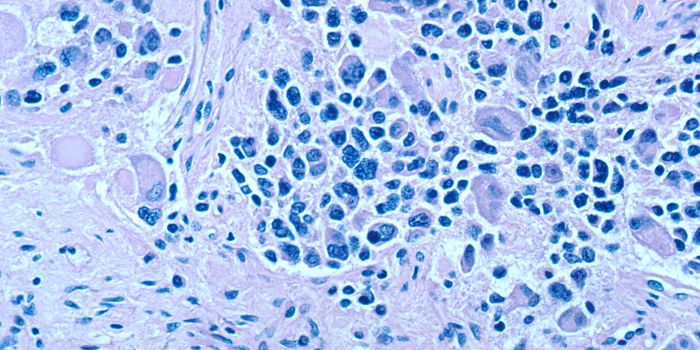

OCT 28, 2021CancerA family of proteins, known as transcription factors, regulate the biological process of converting DNA into RNA. T ...

OCT 19, 2020CancerCancer is a disease characterized by DNA mutations. These mutations, while sometimes small, can cause havoc in a cell&rs ...

SEP 23, 2020CancerThe human body has many ways of letting you know something is wrong. It can send signals to tell you that you are hungry ...

SEP 14, 2020CancerIt is often unknown whether a patient will respond to a treatment until it is in full swing. New research is attempting ...